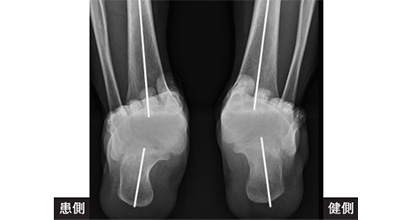

■後面から

踵骨といって踵の骨が内側にたおれてしまう角度を測っています。

TBCという角度を測ります。

参照画像元:秋山 唯、日本フットケア・足病医学会誌4(1):17-21,2023